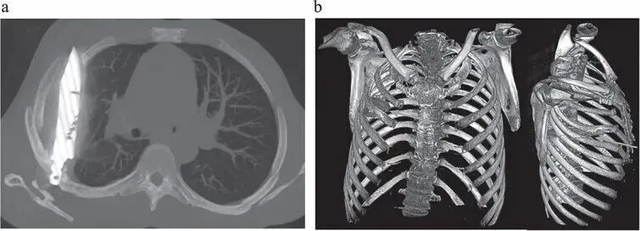

Phim chụp CT (trái) cho thấy lưỡi dao găm vào ngực người đàn ông, trong khi ảnh chụp CT ngực tái tạo 3D (phải) cho thấy cả lưỡi dao và tổn thương xương liên quan mà nó gây ra

Hình ảnh chụp CT cho thấy, mảnh dao đã chui vào giữa khe xương sườn số 5 và 6 từ phía sau, rồi mắc kẹt, đầu nhọn dừng lại ở phía trước giữa xương sườn số 3 và 4. Xung quanh mảnh kim loại, các mô cơ thể đã hình thành bao xơ, giống như cơ chế tự vệ của hệ miễn dịch để “cô lập” dị vật, ngăn ngừa tổn thương lan rộng. Đây chính là lý do bệnh nhân không hề biết trong lồng ngực mình có cả một lưỡi dao suốt ngần ấy năm.